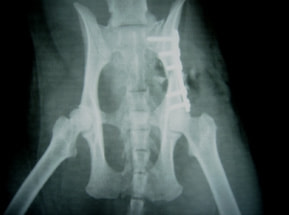

症例:交通事故による椎体脱臼

柴犬:9歳、避妊雌

交通事故直後、胸腰部に激しい疼痛、両後肢に完全麻痺を認め、シェフシェリントン徴候を呈していました。レントゲン検査において、第11-12胸椎間の脱臼が認められました。

脊髄の減圧、脊柱管の再構築・安定化を目的に、片側椎弓切除術およびMatrixMANDIBLE Plateによる椎体固定を実施しました。

隣接椎体を架橋するようにプレートを設置しました。

術後レントゲン写真